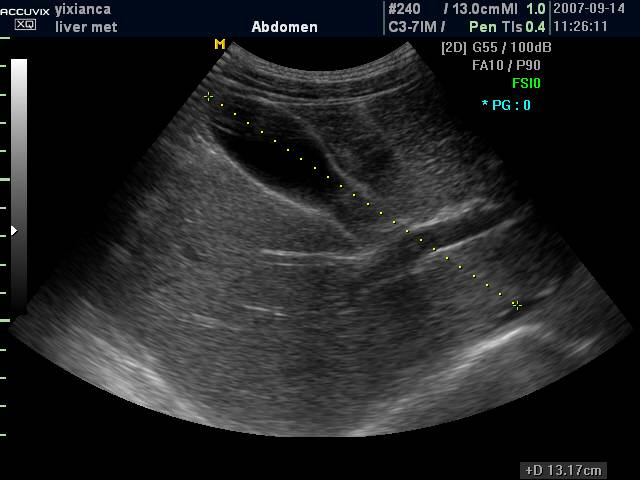

(二)通过肝静脉进行分叶

肝静脉主干在叶间裂或段间裂内行走,易于超声显示,最便于进行肝脏分叶、分段。

1. 肝右静脉行走于右叶间裂内-右前、后叶分界

2. 肝中静脉行走于正中裂的后半部和尾状叶内,右半肝与左半肝分界

3. 肝左静脉近端走行左叶间裂内-左内外叶分界

4. 肝左静脉远端位于左段间裂内-为左外叶上段和下段分界

肝左外叶上下段的超声分界

肝右叶上下段的超声分界